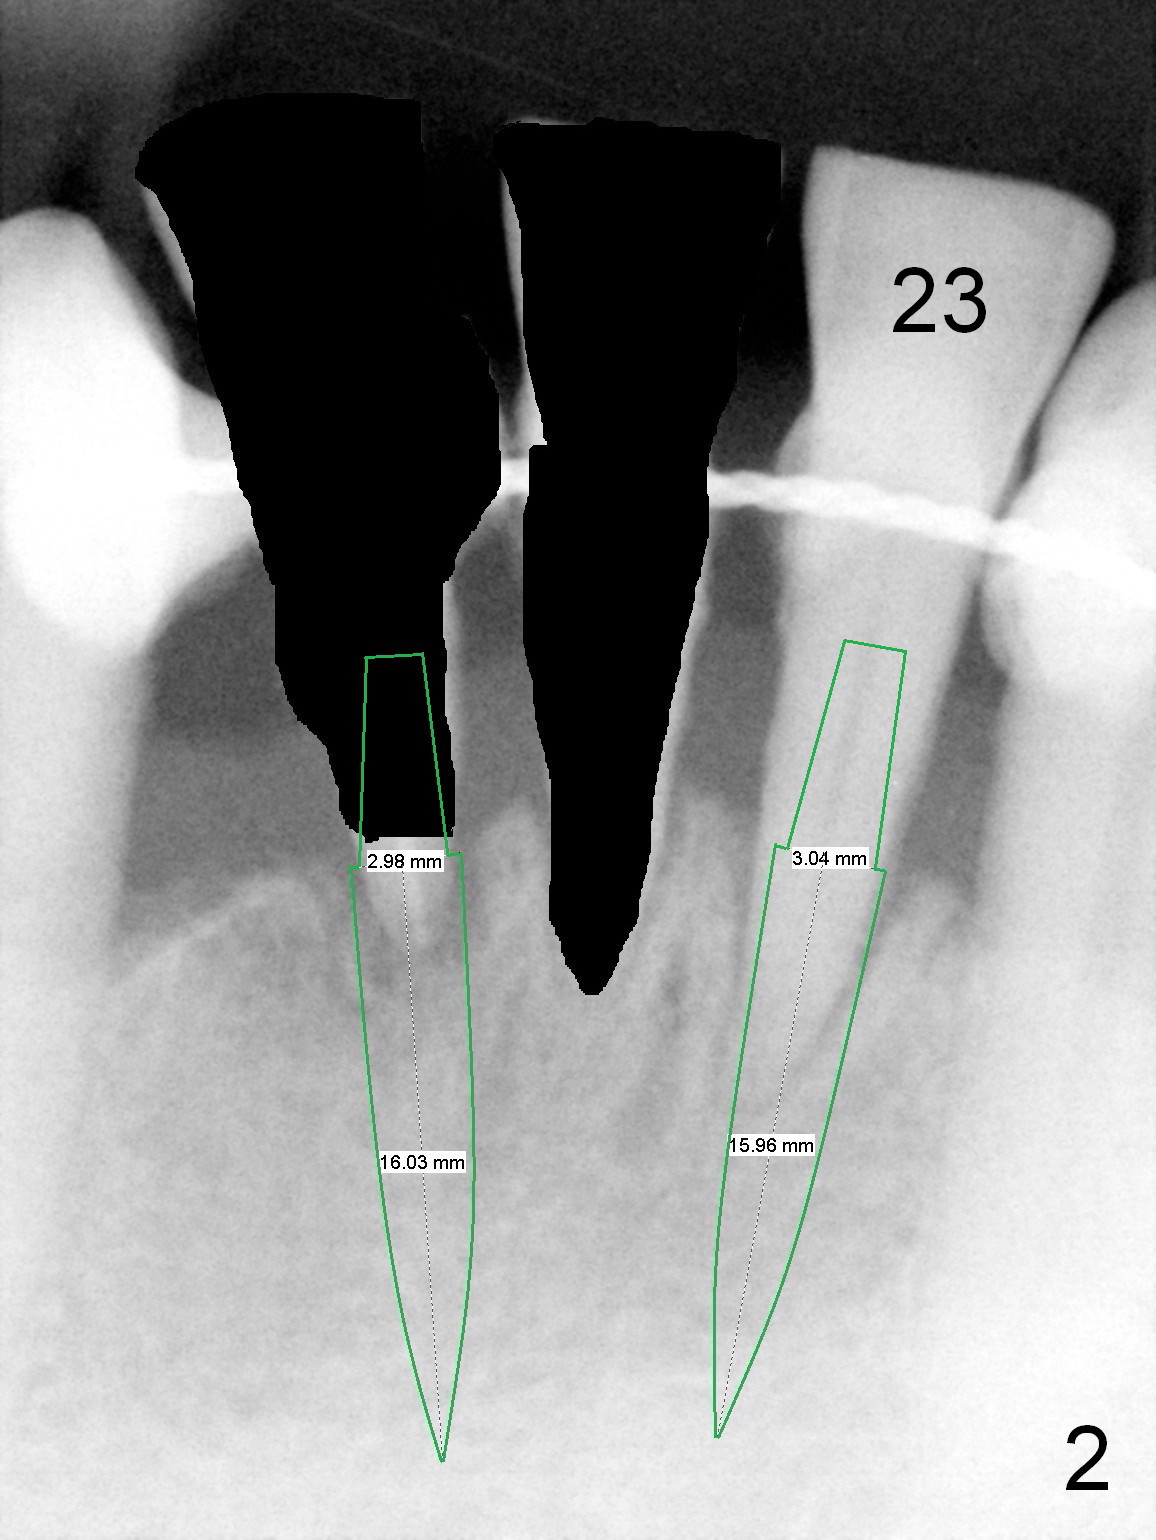

A 59-year-old man requests a partial denture after loss of #24 and 25, seven years after splintng (Fig.1,2). The remaining incisor (tooth #23) has mobility II. After discussion, he agrees with implant-supported FPD. Two of 1-piece implants will be placed at #23 and 25 (Fig.2) to avoid too-close complication. The first implant will be placed at #25. The socket of #23 will be treated with Clindamycin. Surgical and restorative stents are to be fabricated from the model made 7 year earlier (in the shelf of the lab). Use a 3x14 mm dummy implant for trajectory determination. Also prepare angled implants.